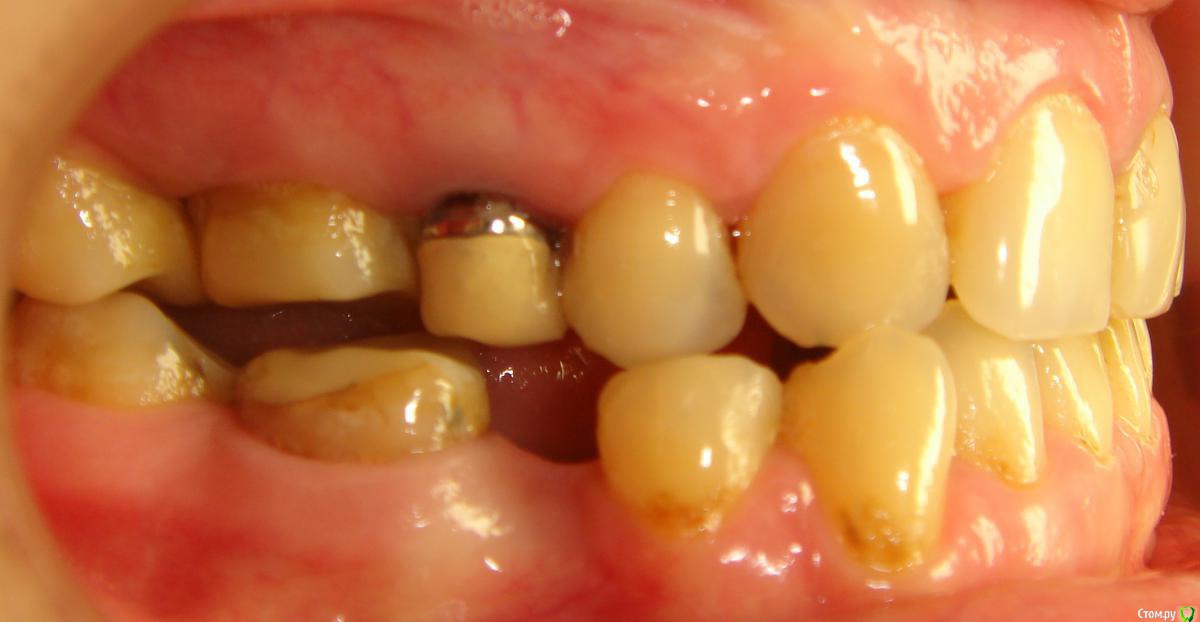

Здравствуйте, Коллеги! Хочу спросить совета по такому случаю. Пациентка 33 года. В детстве удалили 12 зуб, пространство закрыли на съемном аппарате. В подростковом возрасте удалили все остальные отсутствующие зубы. Сейчас носит бюгель. Вопрос такой: заниматься ли мне, как ортодонту формированием полноценного межчелюстного соотношения, или просто решить локальные проблемы и отдать на функциональную реабилитацию ортопеду? И если все-таки заниматься мне, то как??? Лечение такого третьего класса - элементарно для многопетлевой при наличии адекватной опоры, но вот такая адентия заставляет меня сомневаться. Заранее спасибо за ответы!